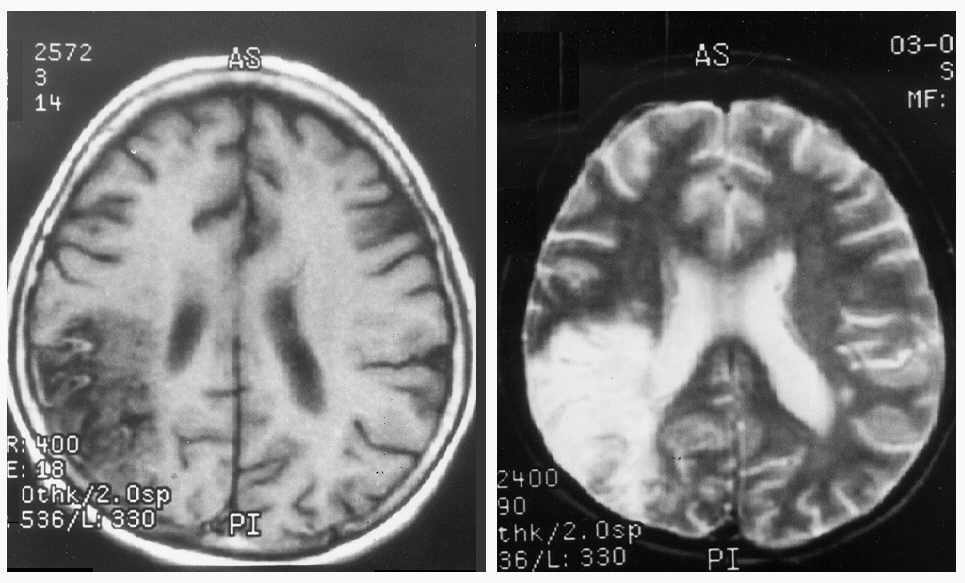

Рисунок к задаче №3 (МРТ головного мозга)